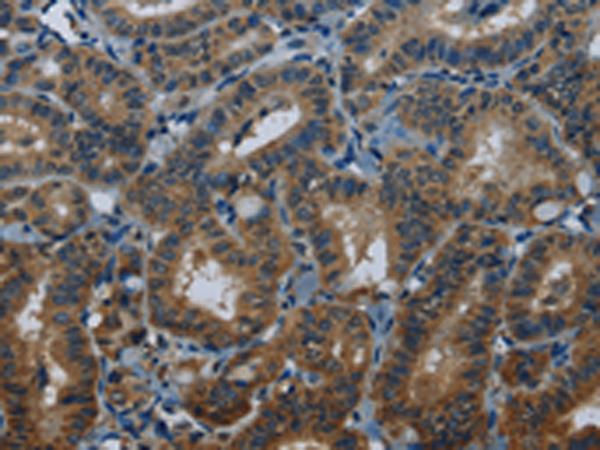

分类: 科研抗体货号: P08523别名: p15; MAAT1应用: WB,IHC反应种属: Human, Mouse